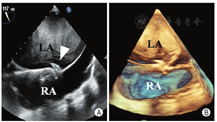

心房分流器置入过程的超声引导与监测:手术开始前,经食管超声多切面观察,排除心腔内血栓、房间隔缺损及房间隔膨胀瘤,同时再次确定适应证。术中经食管超声引导下,房间隔穿刺鞘沿导丝进入右房(图3A),穿刺鞘尖端于卵圆窝后下部进行穿刺(图3B)。穿刺后,预先塑形的加硬钢丝经房间隔穿剌部位至左心房内,其后递送10 mm外周动脉球囊至房间隔处,以8个标准大气压行反复球囊扩张。超声实时监测扩张部位、过程、大小。退出球囊后送入输送系统,选择20-6 mm的D-shant心房分流器,在经食管超声监测下,将其释放于房间隔两侧(图4A,B),经食管超声显示分流器形态、位置正常,分流孔径约6 mm,并清晰显示左向右分流信号(图5),三维超声观察分流器形态及其与周围组织毗邻关系;即刻右心导管测压,左房压由分流器置入前15 mmHg降至置入后8 mmHg(1 mmHg=0.133 kPa),释放分流器。术后送监护病房观察。患者自诉症状明显改善,1 d后从监护室转回普通病房,3 d后出院。3个月后复查心脏超声,分流器形态位置正常,患者自觉生活质量提高。